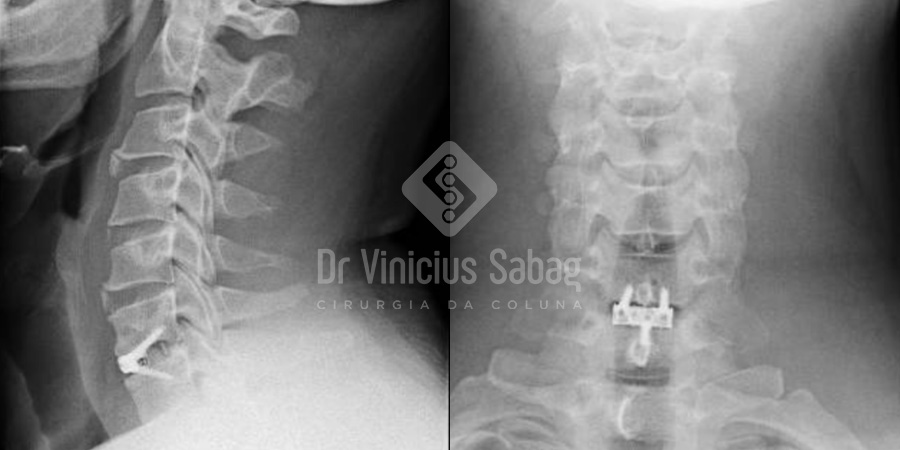

Radiografia pós-operatória.

O controle por imagem confirmou o sucesso do procedimento, evidenciando a completa retirada da hérnia discal e a descompressão efetiva das estruturas neurais.